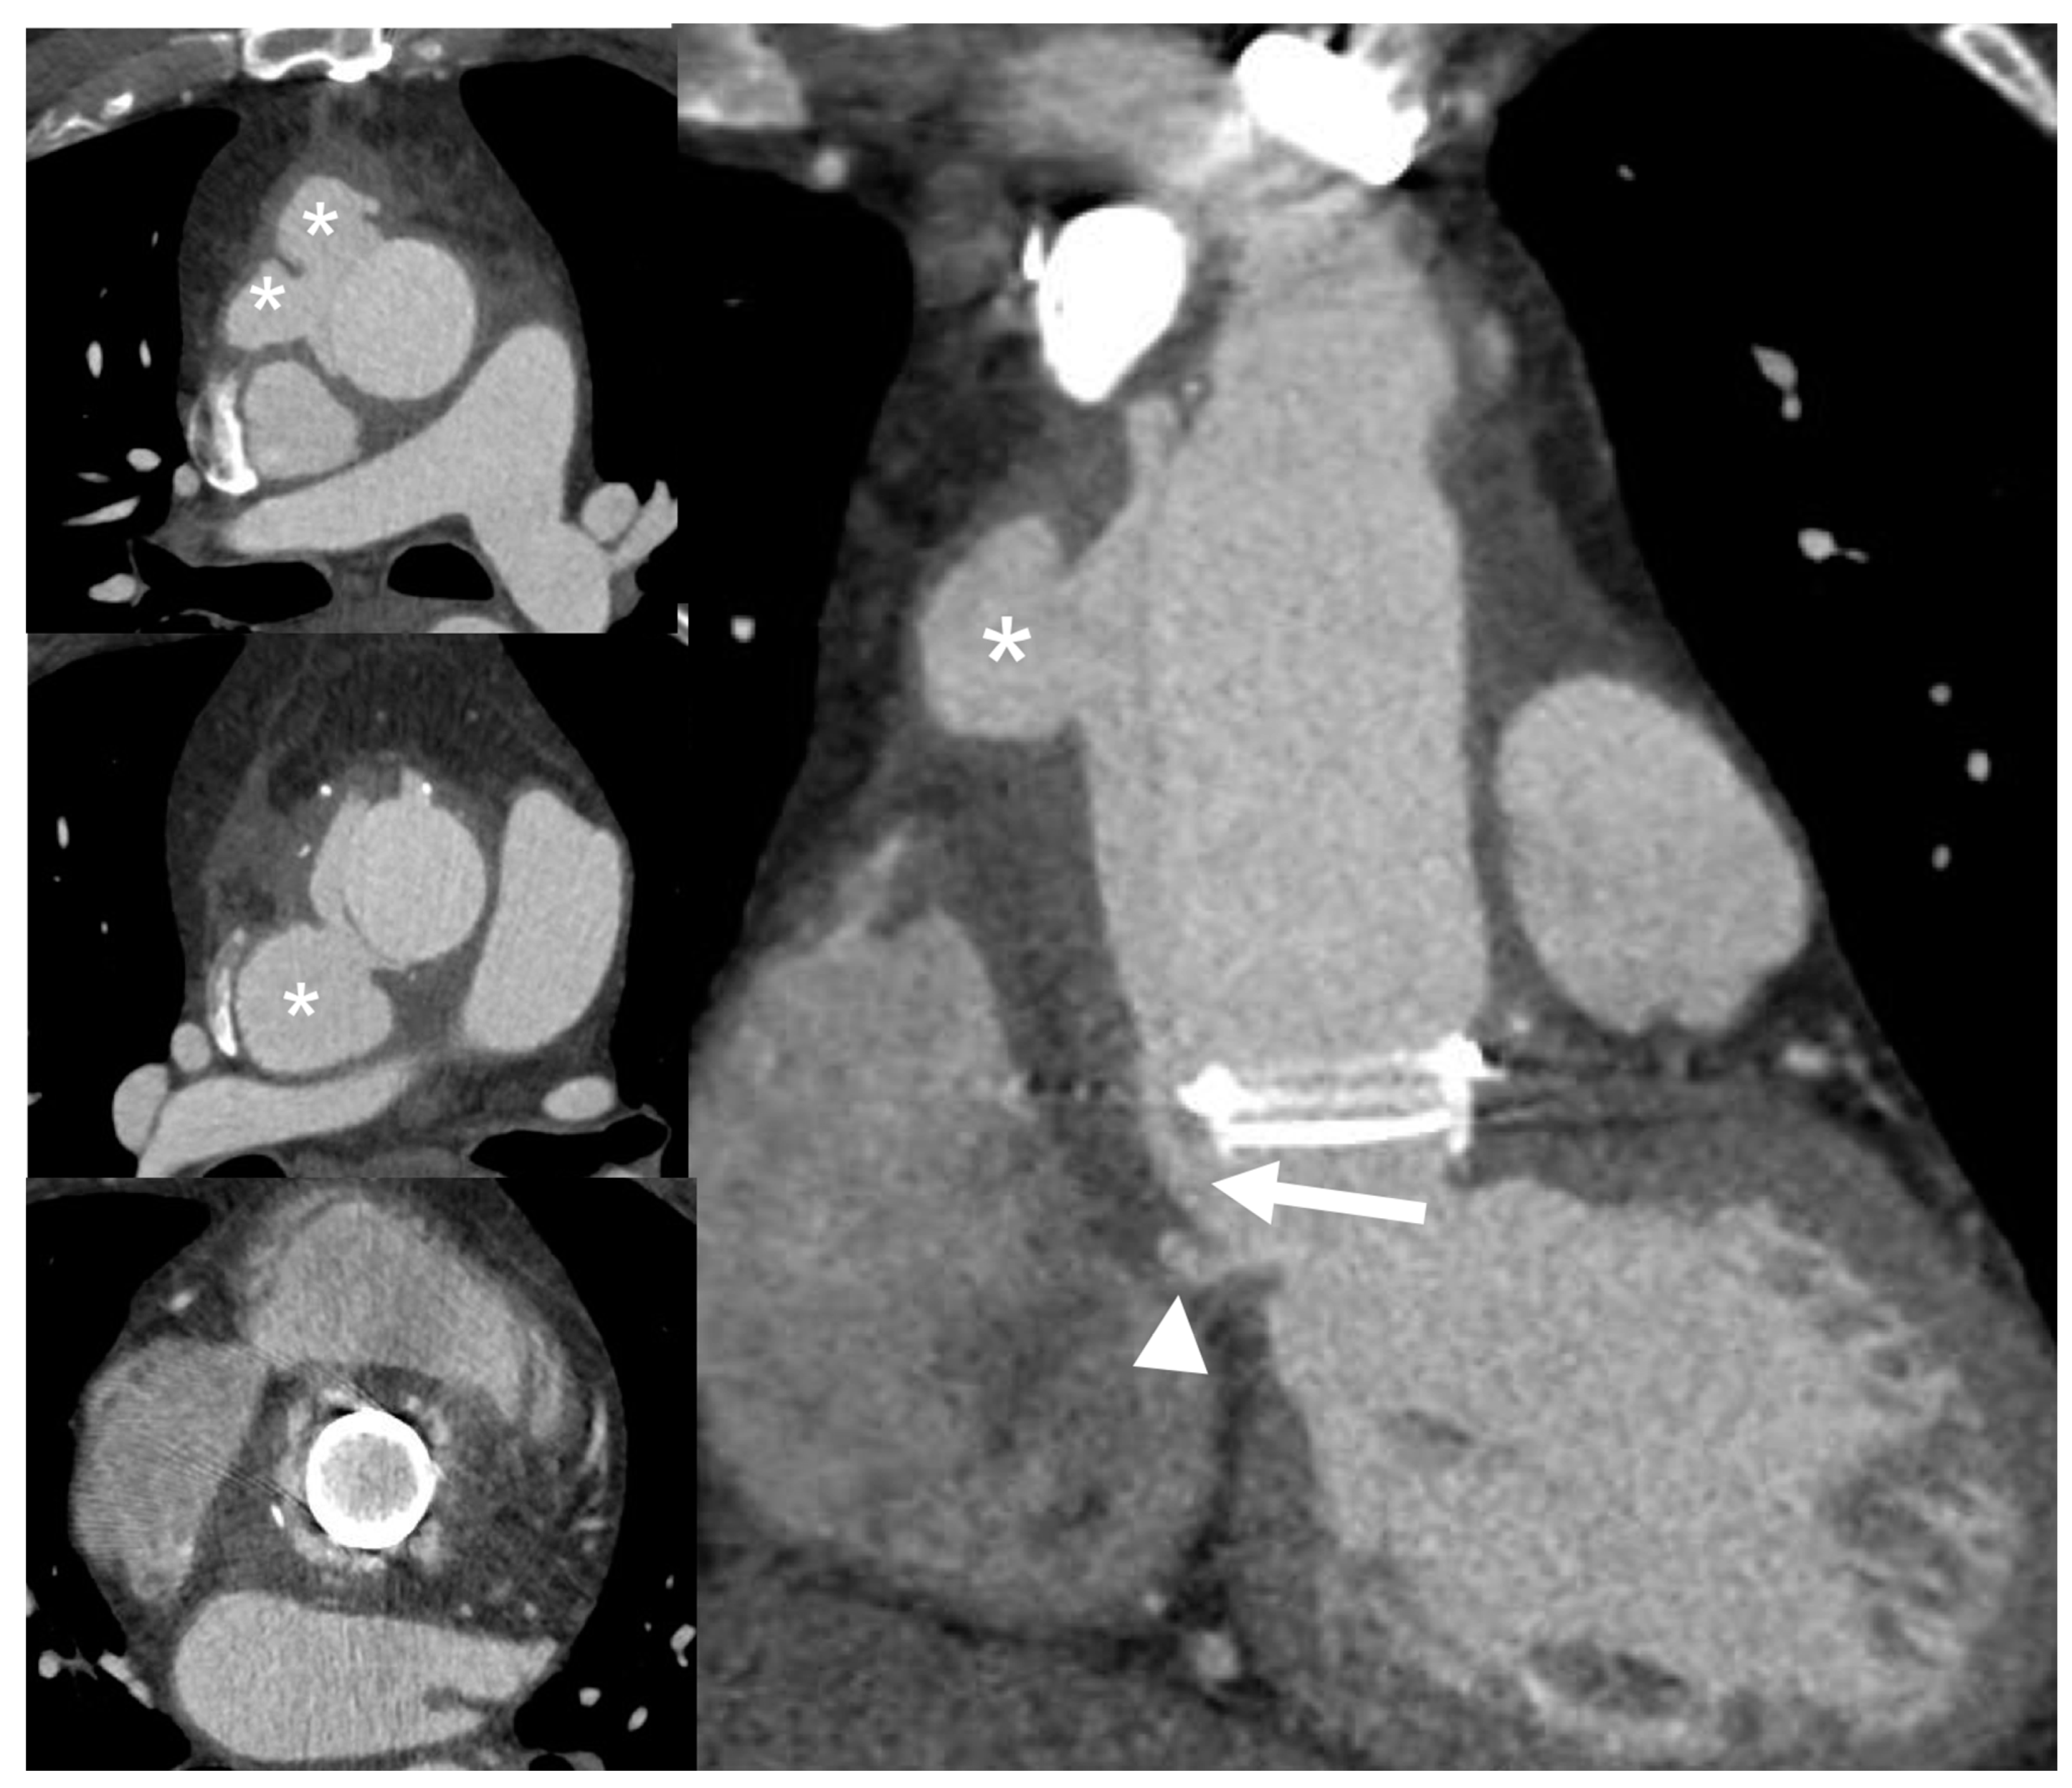

| Left-sided IE | Good visualization of mitral and aortic valve. Valvular dysfuction assessment. Identification of complication (i.e., valvular regurgitation). | Difficult differential diagnosis in presence of marantic vegetations or high calcification. | Detection of vegetations and valve perforation. Assessment of perivalvular extent of disease (abscesses, pseudoaneursysm, fistula). | Inferior to TTE/TOE in detecting small vegetations (<2 mm). | Prognostic assessment: simultaneous detection of embolism, metastatic lesions and portal of entry. | Limited sensitivity for small vegetations. | Evaluation of distant emboli and portal of entry. | Limited role because of low sensitivity for small vegetations. | Capability to assess vegetations (inferior to TTE/TOE). Capability to assess local complications. Independent by acoustic window. May detect concomitant myocardial inflammation. | Not included in current guidelines for IE diagnosis. |

| PVE | Routinely used for follow up; it allows sequential assessment of prosthesis function. TOE is often required to correctly assess the prosthesis. | Limited by prosthetic material artifacts (i.e., acoustic shadow). Early complication (i.e., abscess) can be difficult to identify. | Identification of complications (paravalvular leakage, abscesses, pseudoaneurysm, dehiscence, and extension to adjacent structures). Capability to visualize large vegetations (>10 mm). | Low image quality for beam hardening artifacts. Limited in assessing small vegetations (<4 mm). | High diagnostic accuracy. Good assessment of perivalvular/periprosthetic complications. Reduction of rate of misdiagnosed PVE. Role in prediction of MACEs. Prognostic significance. | Host reaction may reduce specificity (risk of false-positive studies until 3 months after surgery). | High specificity for infection. Reduction of rate of misdiagnosed PVE. Differential diagnosis between septic and sterile vegetations. | Limited sensitivity for small lesions. | Image quality severely hampered by susceptibility artifacts (especially from mechanical prostheses). | |